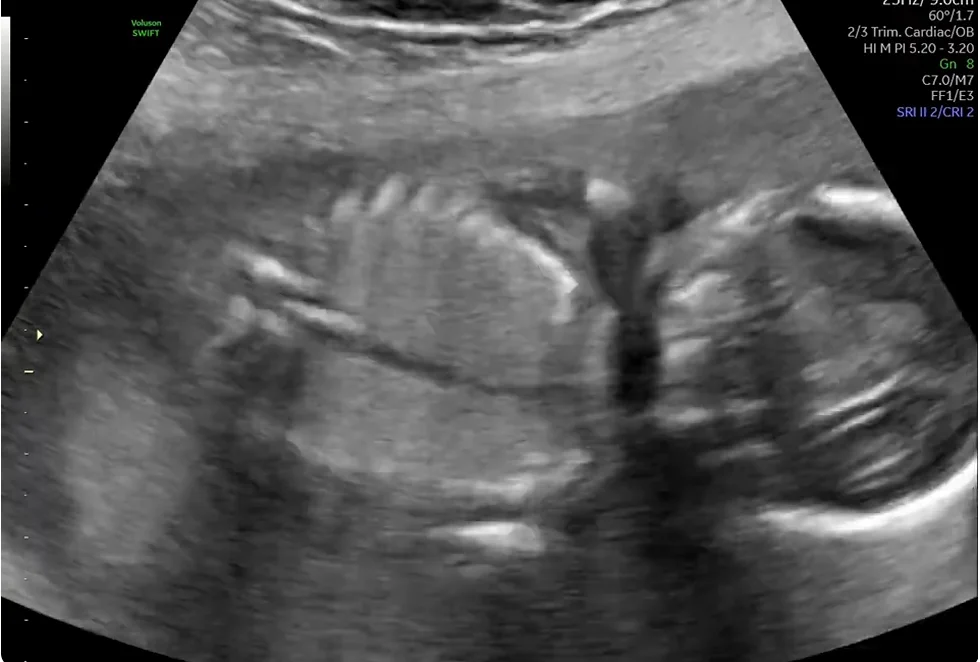

• Thoát vị hoành bẩm sinh thai nhi (Congenital Diaphragmatic Hernia)

• Bất thường nang tuyến phổi bẩm sinh thai nhi (Congenital Pulmonary Airway Malformation)

• Phổi biệt trí thai nhi (Bronchopulmonary sequestration)

• Nang phế quản thai nhi (Bronchogenic Cyst)